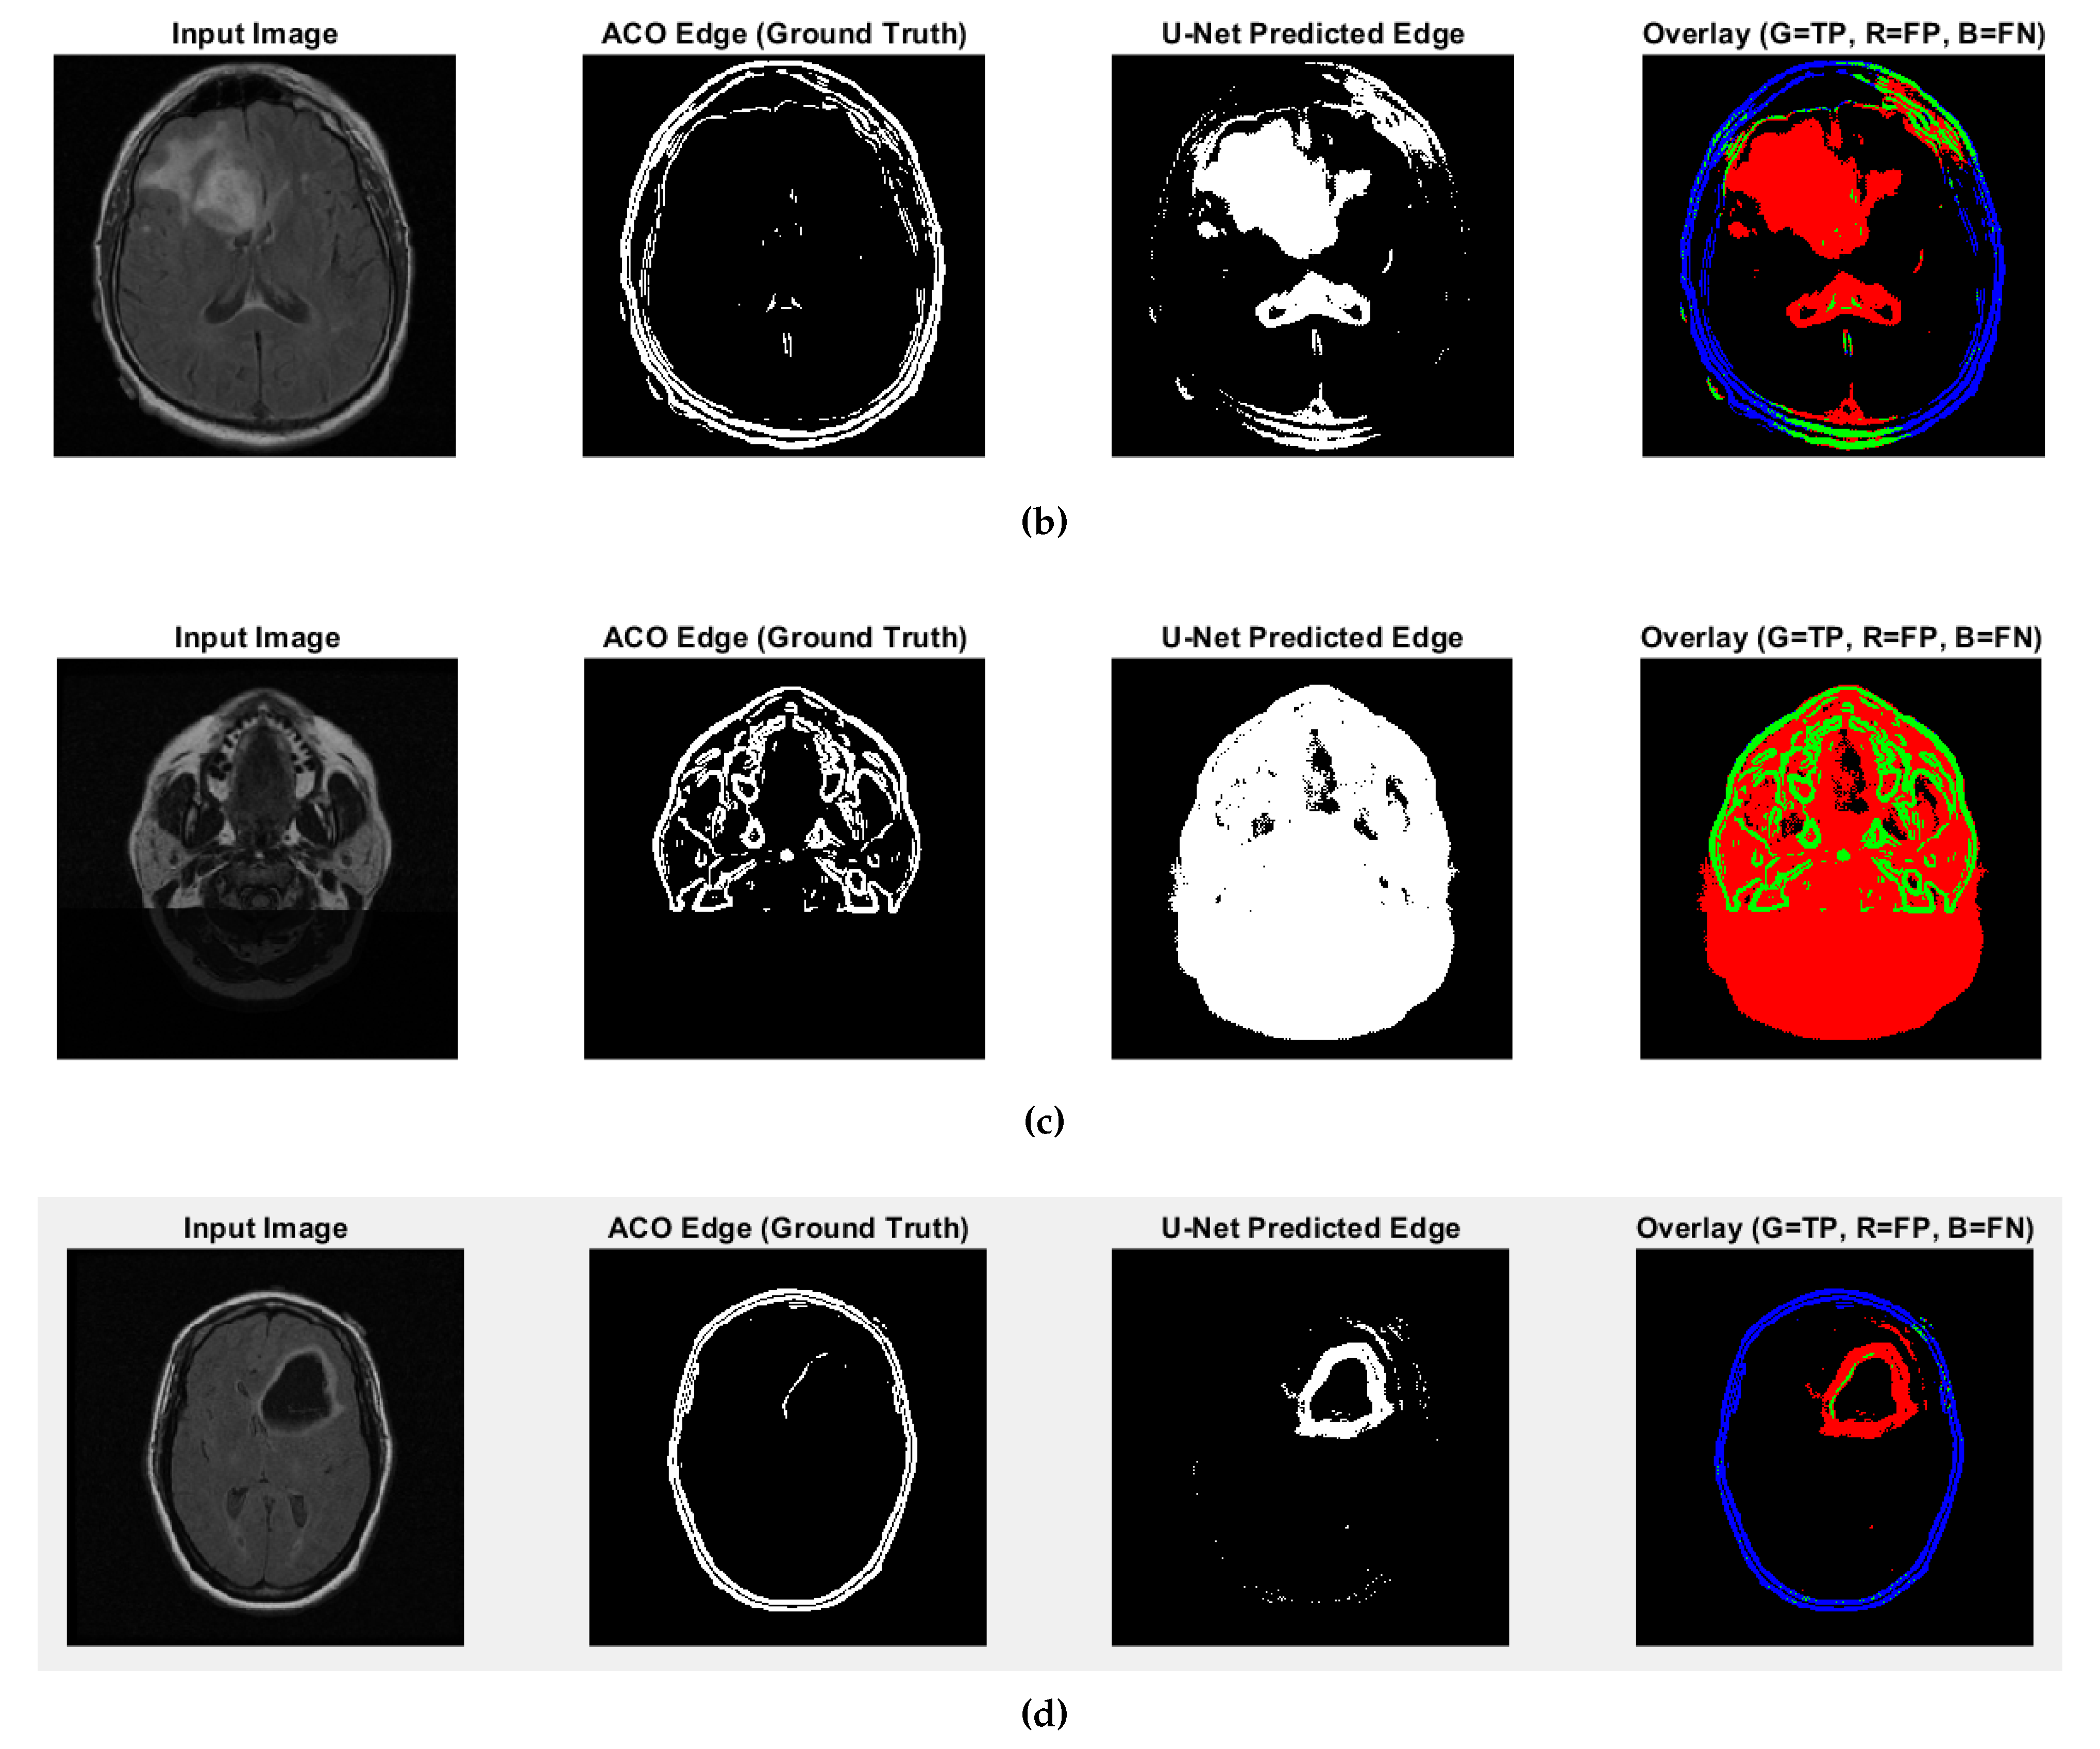

Figure 7. CS1 results when comparing ACO and U-Net (Red: U-Net Predicted Edge, Green: ACO Edge; additional results are shown in Figure A3).

Predicted edges from the U-Net with ResNet18 encoder–decoder differ in thickness compared to the ACO-derived ground truth across test cases. In some cases, the predicted edges are significantly thicker (over-segmented), while in others, they are fewer or thinner (under-segmented). This variability affects the similarity metrics as follows:

• High recall values (e.g., 0.9880 and 0.9963 for CS1 and DU1 images) indicate that in these cases, the model successfully identified most ground truth edge pixels—though often with excessive prediction (over-segmentation);

• Very low recall (e.g., 0.0483 for DU2 image) shows that in some cases, the model fails to detect most of the true edge pixels—under-segmentation;

• Low precision values across all cases (from 0.0952 to 0.2342) suggest that many of the predicted edge pixels do not match the ground truth, indicating high false positive rates;

• F1-score and Jaccard Index are low overall (F1 from 0.0641 to 0.3786; Jaccard from 0.0331 to 0.2335), pointing to a general mismatch between predicted and true edge locations;

• SSIM and Max NCC vary from moderate to low (SSIM up to 0.7892, NCC mostly below 0.33), reflecting inconsistent structural similarity and limited pixel-level correlation across cases.

The U-Net model can successfully detect edge regions but shows inconsistent behavior across cases—over-predicting in some and under-predicting in others. This results in imprecise edge localization. Future improvements will focus on training refinement, edge-aware loss functions, and post-processing steps such as edge thinning to enhance precision and structural accuracy.

Figure A3. Fuzzy edge results from iMIA (results of comparing ACO and U-Net): (bTCGA_CS_4941_ 19960909_14 (CS2), (c) TCGA_DU_5872_19950223_1 (DU1), (d) TCGA_DU_5872_19950223_35 (DU2) (Red: U-Net Predicted Edge, Green: ACO Edge; refer to the image (a) CS1 result in Figure 7).